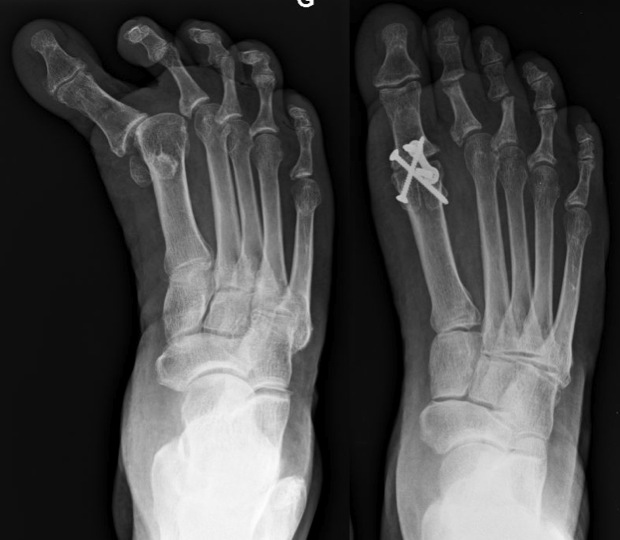

Généralement, un hallux varus survient dans les suites d’une opération pour un hallux valgus, et est de fait une complication due à un excès de correction. D’autres causes sont cependant possibles : post-traumatiques, en association à certaines maladies systémiques inflammatoires comme la polyarthrite rhumatoïde ou le psoriasis, quelques cas sont congénitaux…

Si cette déformation est peu gênante et si la déformation reste souple, vous pouvez simplement porter des chaussures à bouts larges ce qui limite le frottement. Si la déformation et la raideur augmentent, les chaussures adaptées ne suffissent plus. On peut alors proposer une solution chirurgicale. Il faut préalablement vérifier la mobilité et la réductibilité de l’articulation métatarsophalangienne. Si elle est raide et douloureuse, la meilleure solution est alors l’arthrodèse.